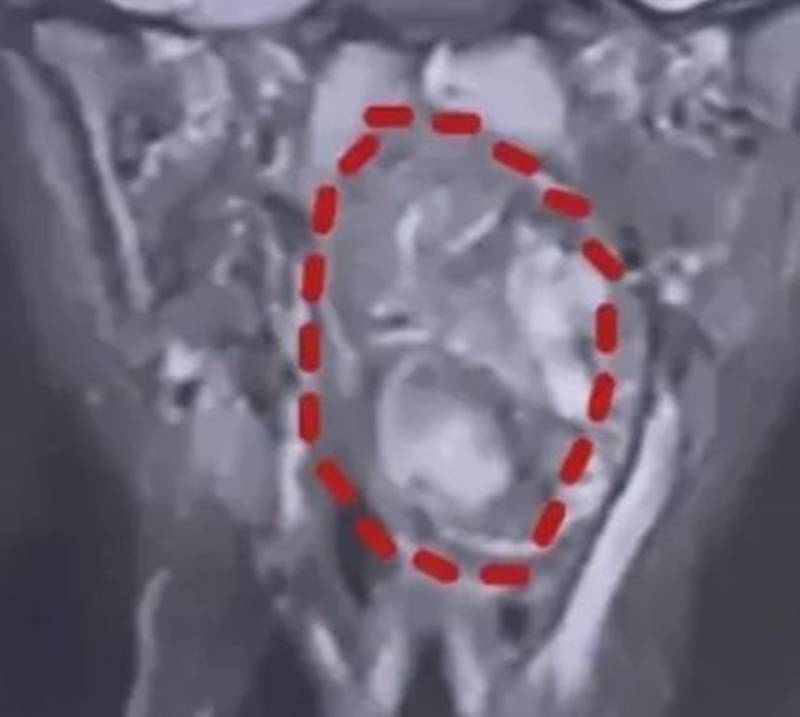

ดร.เฉิน กล่าวว่า เทอราโตมามักพบในช่องท้อง การพบเทอราโตมาในลำคอของเด็กและมีขนาดใหญ่เช่นนี้เป็นเรื่องที่หายากมาก ภาพถ่ายทางการแพทย์แสดงให้เห็นว่า ช่องคอหอยของเขาที่มีขนาดประมาณ 8 เซนติเมตร เต็มไปด้วยเนื้องอกขนาด 6.6 เซนติเมตร เหลือเพียงช่องเปิดแคบ ๆ ในทางเดินหายใจของเขา ซึ่งก่อให้เกิดความเสี่ยงต่อการขาดอากาศหายใจและเสียชีวิตในทันที